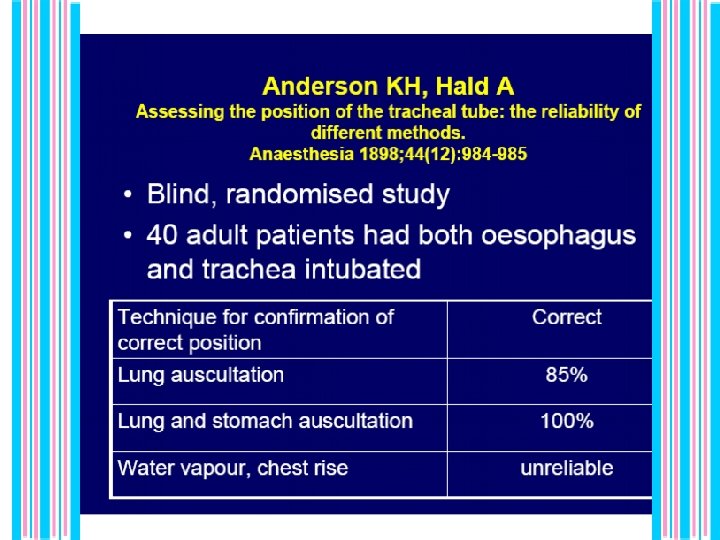

Signs of correct tube position l Chest rise with each breath l Breath sounds over both lung fields l No gastric distention with ventilation l Vapor condensing on inside of tube during exhalation l Carbon dioxide detector will change color (or reads more than 2%-3% during exhalation)

• False positive (tube in esophagus) • technical error. • False negative (tube in trachea CO 2 reading low) • severe bronchospasm, • hyperventilation, • technical error, • huge leak around ett, • cardiopulmonary arrest. _ _ _ Figure 1. Sensitivity = 94%, Specificity = 98%, P P Value = 98% , N P Value = 94%